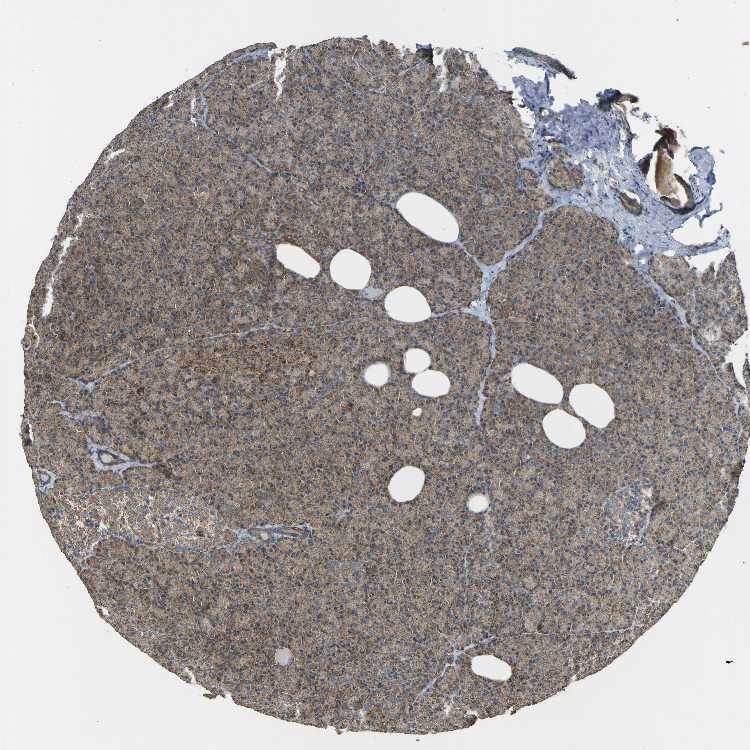

PANCREAS - Antibody stainingi

Antibody staining in the annotated cell types in the current human tissue is reported as not detected, low, medium, or high, based on conventional immunohistochemistry profiling in selected tissues. This score is based on the combination of the staining intensity and fraction of stained cells.

Each image is clickable and will lead to virtual microscopy that enables deeper exploration of all samples and also displays staining intensity scores, fraction scores and subcellular localization as well as patient and tissue information for each sample.

Antibody HPA011215Antibody CAB009623

Exocrine glandular cells MediumMedium

Pancreatic endocrine cells LowMedium